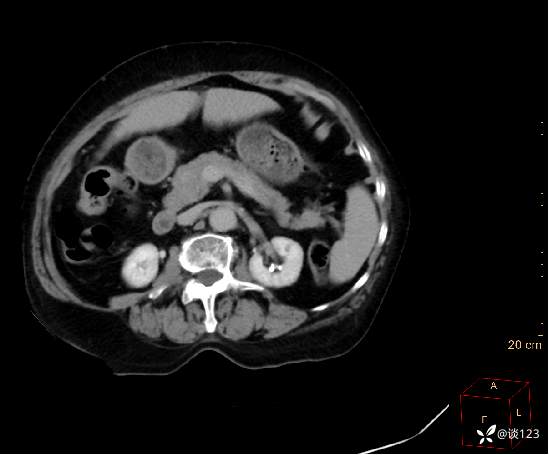

先做的CT:

C-

A

V

D

重新针对CT进行多参数后处理

这类病变不结合病史的情况,即使在CT静脉期有所异常也容易忽略;同时针对该类疾病使用胰腺增强方案应该更佳,好的诊断先决条件还是技术,技术不够CT新技术来凑。